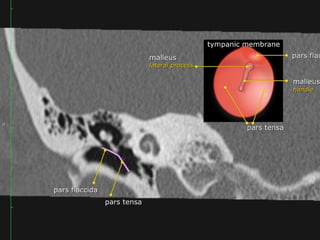

Tympanic membrane

 The tympanic membrane or eardrum is a cone-shaped membrane

that separates the external ear from the middle ear.

 The pars flaccida is the upper fragile part that is associated with

eustachian tube dysfunction and cholesteatoma.

 The pars tensa is larger and more rubust and associated with

perforations.

The handle or manubrium of the malleus is connected to the central

part of the tympanic membrane, which is called the umbo.